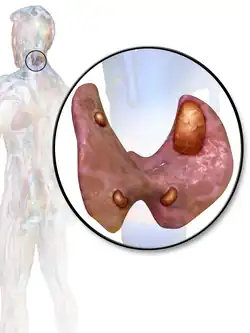

3D diagram of hyperparathyroidism

The parathyroid is composed of 4 glands with 2 located superiorly and 2 located inferiorly.[23] The parathyroid glands are located on the posterior thyroid and are derived from the endoderm of the 3rd and 4th pharyngeal pouches.[23] Specifically, the inferior parathyroid glands are derived from the 3rd pharyngeal pouch and the superior parathyroid glands are derived from the 4th pharyngeal pouch dorsal wing.[24] The ultimopharyngeal body is derived from the 4th pharyngeal pouch ventral wing and the parafollicular cells ( C-cells) are derived when the ultimopharyngeal bodies fuse with the posterolateral thyroid.[24] The parathyroid glands separates from the pharyngeal wall and attaches to the posterior thyroid during the 7th week of human embryonic development.[23]